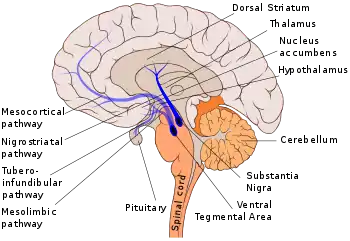

The midbrain tegmentum is also an important part of the dopaminergic system which is essential for feelings of reward and pleasure. Two regions in the midbrain tegmentum are of particular interest. The first one is the substantia nigra which is an important part of the nigrostriatal pathway. This pathway serves to coordinate motor movements and when left unbalanced, motor deficits would follow. For instance, when the dopamine neurons are lost from the substantia nigra, the condition of extreme muscle rigidity occurs as in the Parkinson's disease. The second region is the ventral tegmental area (VTA; or simply ventral tegmentum) which is at the hub of the mesolimbic pathway. Specifically, the VTA is the origin of dopaminergic cell bodies from which signals reach the anterior parts of the brain (e.g., frontal lobes) as well as the posterior parts (e.g., cerebellum). Because of this pathway regulates the experience of reward and pleasure, it is not surprising to see that food and drugs affect it the most in terms of a loss of impulse control. That is, the mesolimbic pathway is essential in regulating drug addiction. The potential mechanism is through the associative learning of the environmental cues and reward. For instance, through each drug use, individuals increasingly associate the cues related to each drug use (e.g., the room in which the drug is taken or the people with which individuals take drug). Over time, the drug enhances the dopamine-related, classically-conditioned cues associated with drug taking. As a result, later encounters with these cues will produce and heighten dopamine activity and subsequently prompt individuals to crave drugs. Moreover, excessive mesolimbic dopamine activity plays a role in schizophrenia, a behavioral disorder characterized by delusions, hallucinations, blunted emotion, agitation, etc. On the other hand, a lack of mesolimbic dopamine activity may induce deficits in attention.[1]